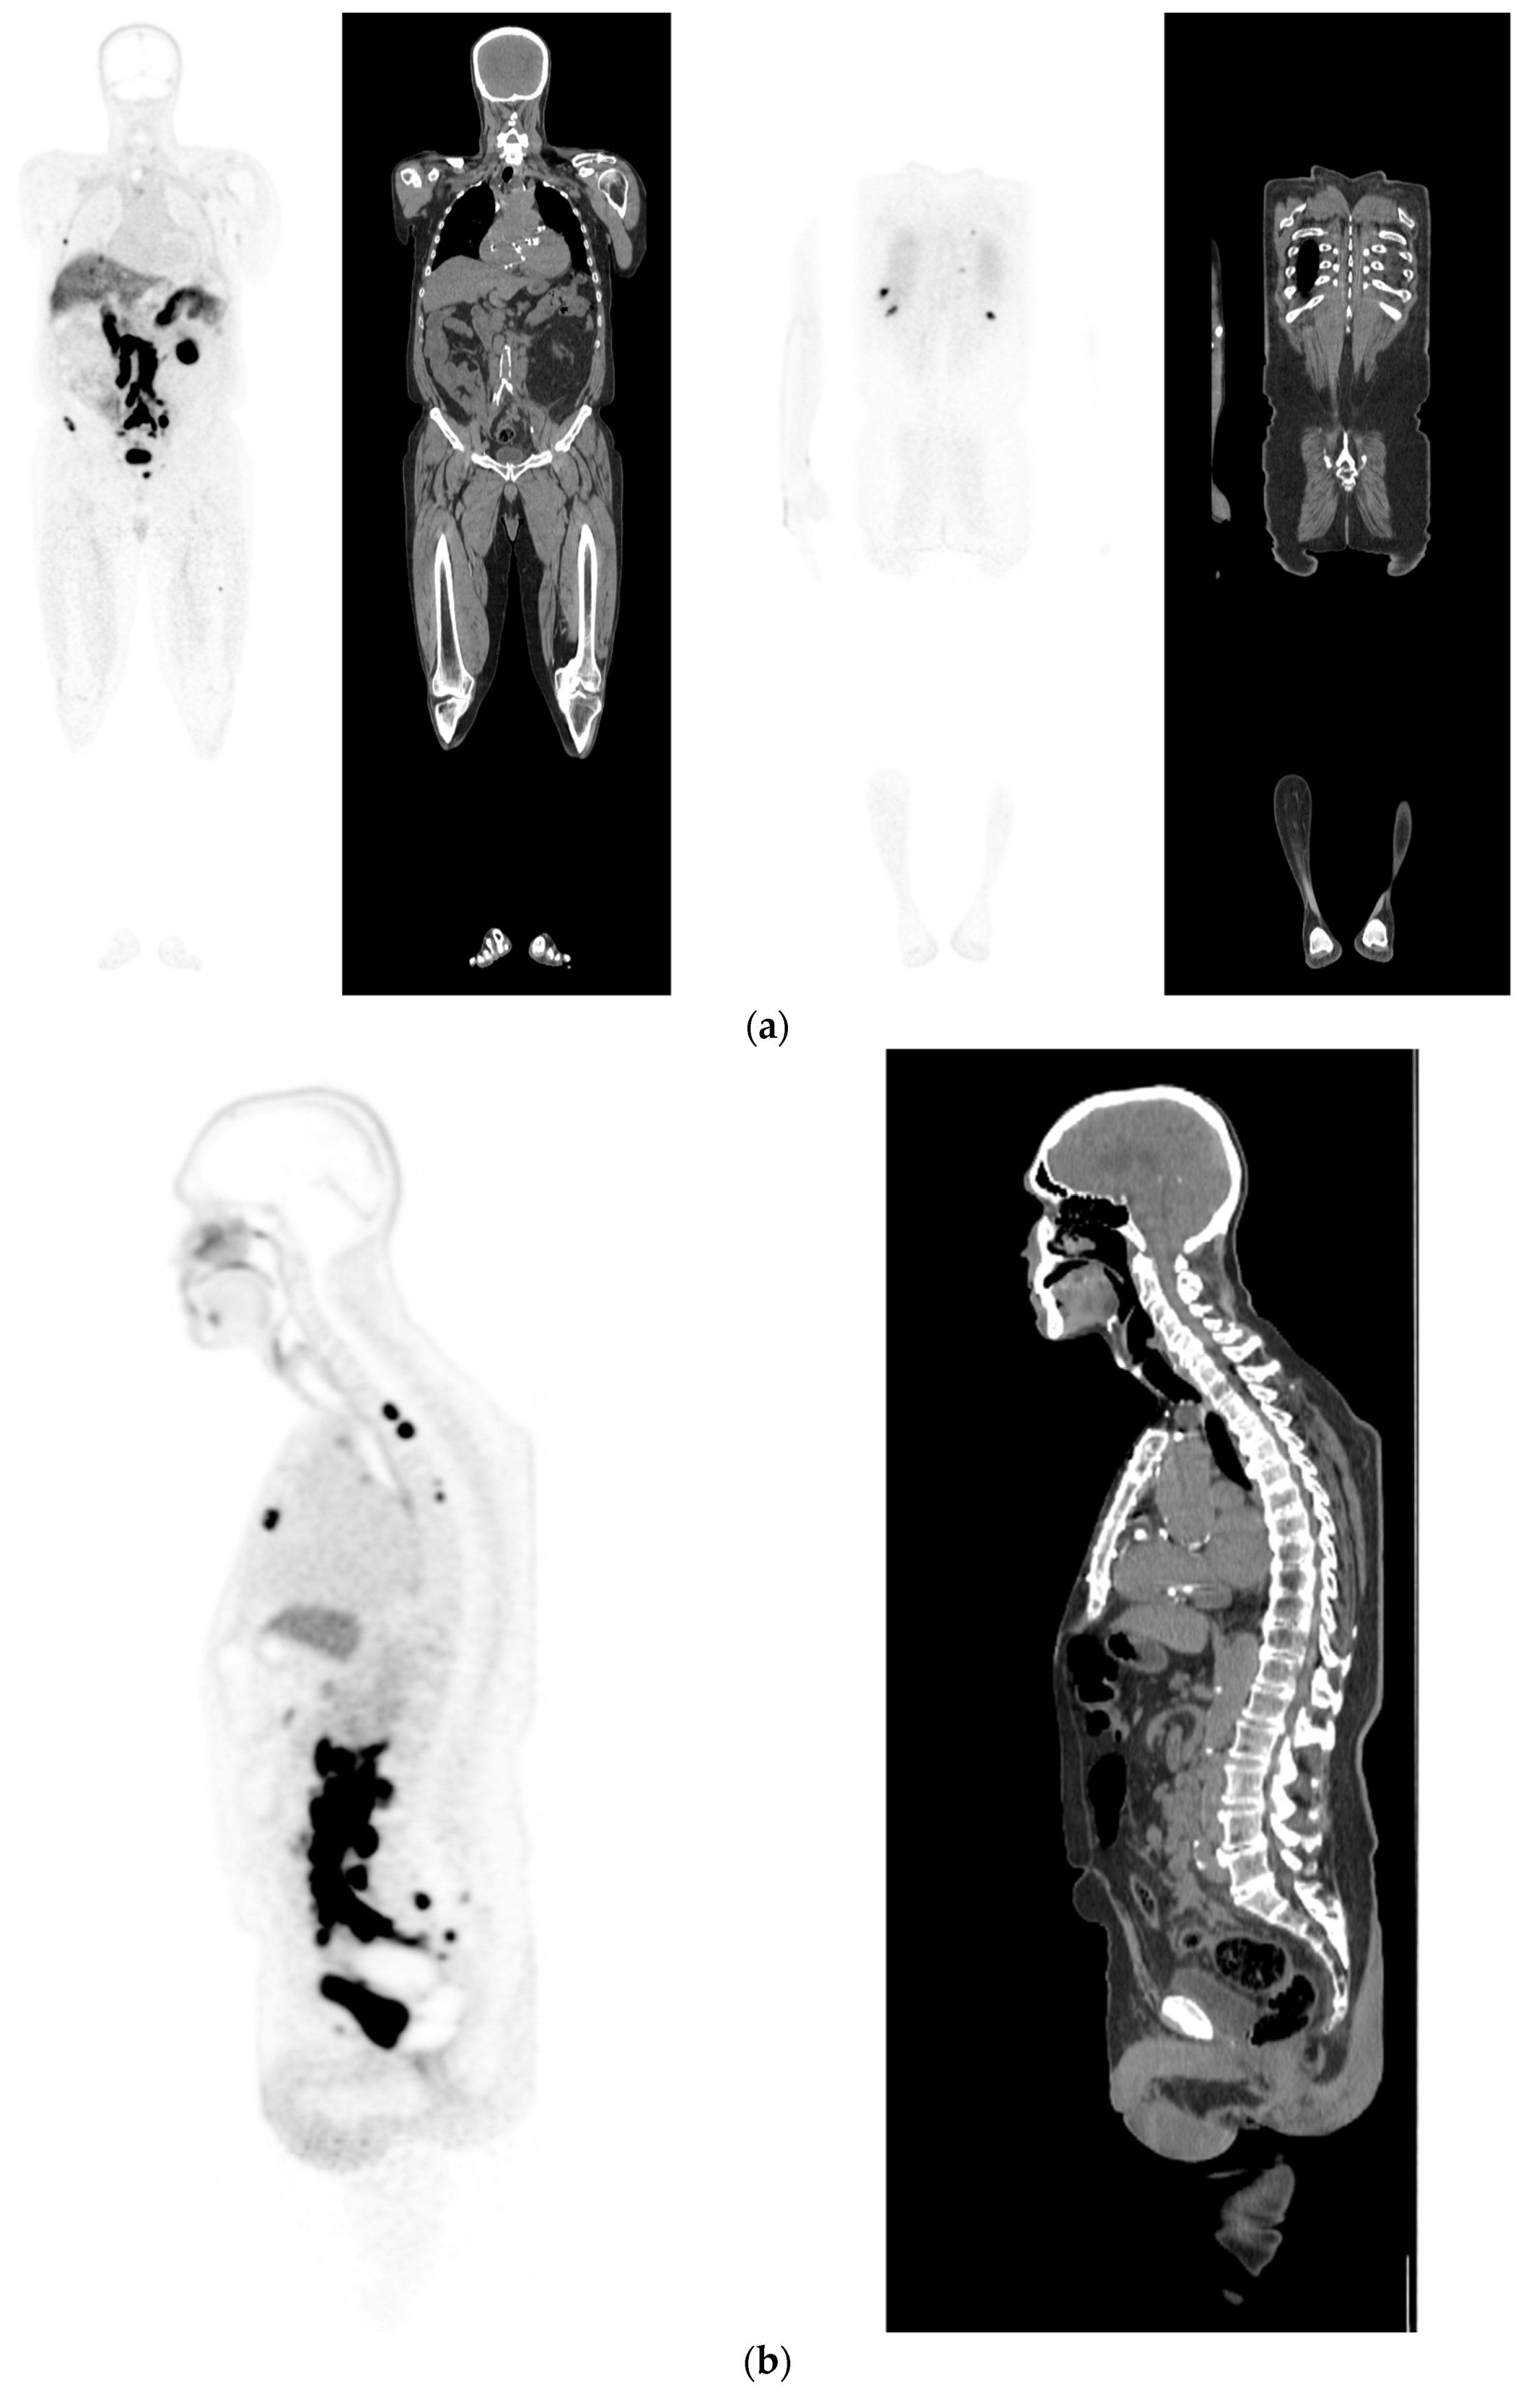

Figure 4.

Biochemical recurrence—serial scans. 58 yr old M—radical prostatectomy and node disSection 10 yrs prior; scans done in July 2020 when PSA 0.24 and Sep 2021 when PSA 0.38. (a): PSMA PET-CT: July 2020-68Ga-PSMA-226 MBq; uptake 49 min; BMI = 35.1; Wt 105 kg; coronal images and transaxial images at level of prostate bed show tracer excretion; rest of study clear. (b): PSMA PET-CT: Sep 2021-68Ga-PSMA-238 MBq; uptake 50 min; BMI = 35.2; Wt 107 kg; coronal images and transaxial images at level of prostate bed show tracer excretion but with a new small focus of uptake SUV= 6.0 in left side of prostate bed; rest of study clear.

Figure 5.

Biochemical recurrence—negative scan; normal distribution of tracer. 75 yr old M—radical prostatectomy 7 yrs prior; PSA 0.42. PSMA PET-CT: 68Ga-PSMA - 219 MBq; uptake 48 min; BMI = 22.6; Wt 63 kg. (a,b): coronal images show physiological uptake in parotid glands, bowel and kidneys and tracer pooling in bladder; X-hairs show uptake in cervical (SUV = 2.3) and sacral (SUV = 2.5) nerve roots and sympathetic ganglia in upper abdomen SUV = 4.6. (c,d): enlarged coronal, sagittal and transaxial images of prostate bed; X-hairs identify locations; no abnormal tracer uptake but pooling of trace in bladder problematic; Note—scale in sagittal images on (c) has been deliberately altered to ensure there are no adjacent focal regions of uptake to suggest local tumor recurrence.